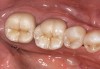

Next is the flexure risk assessment. Each tooth and existing restoration is evaluated for signs of past overt tooth flexure. Signs of excessive tooth flexure can be excessive enamel crazing (Figure 2), tooth and restoration wear, tooth and restoration fracture, microleakage at restoration margins, recession, and abfraction lesions. Often, the etiology is multifactorial and controversial. However, if several of these conditions exist, there is an increased risk of flexure on the restorations that are placed, which may overload weaker materials. Evaluation of this possibility is also based on the amount of remaining tooth structure. The more intact the enamel is, the less potential for flexure. The amount of tooth preparation can directly affect tooth flexure and stress concentration. There is much potential subjectivity in any observational assessment of clinical conditions; however, an assessment of flexure potential for each tooth to be restored is needed. A subjective assignment of Low, Medium, or High Risk for flexure is based on the evaluated parameters, as outlined below.

Figure 2  Image demonstrating excessive enamel crazing, leakage, and staining. Flexure, tensile, and shear risks would be medium to high. The substrate would depend on preparation.

Figure 2